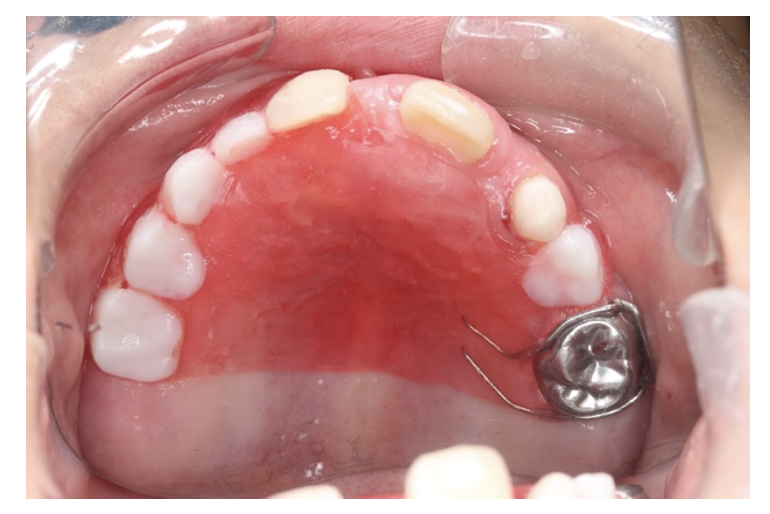

③可撤保隙装置(小児義歯)

少数〜多数の乳歯がなくなった場合に使用します。

入れ歯を使用してスペースを保ちます。

①、②とは異なり取り外し式の装置です。毎日使用していないとあわなくなってしまいます。

子ども自身での管理が必要なため、3歳未満は使用できません。

現時点では保険適応外のことが多いです。